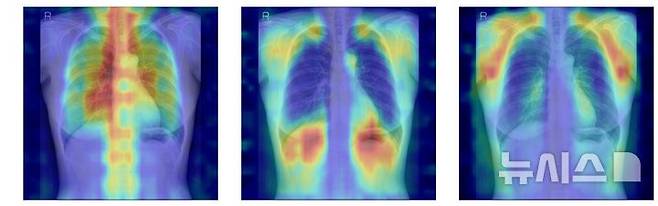

![[서울=뉴시스] 흉부X선에서 파운데이션 모델이 골다공증 판독을 위해 주목한 영역을 시각화한 이미지. (사진= 서울대병원 제공)](https://img3.daumcdn.net/thumb/R658x0.q70/?fname=https://t1.daumcdn.net/news/202511/28/newsis/20251128102641102nimg.jpg)

연구팀은 여기에 더해 AI가 실제로 어떤 뼈를 근거로 삼아 판단하는지까지 확인할 수 있도록 '설명 가능성' 평가 체계를 설계했다. 뼈를 모두 가린 상태에서 특정 뼈 부위를 추가해 성능이 얼마나 향상하는지 확인하는 '차단 분석 방식'과 AI의 주목 영역이 실제 뼈 위치와 얼마나 일치하는지를 계산하는 '유의성 지도 방식'(IoUbone)을 통해, AI가 임상적으로 중요한 뼈 구조를 근거로 판단하는지를 정량적으로 검증했다.